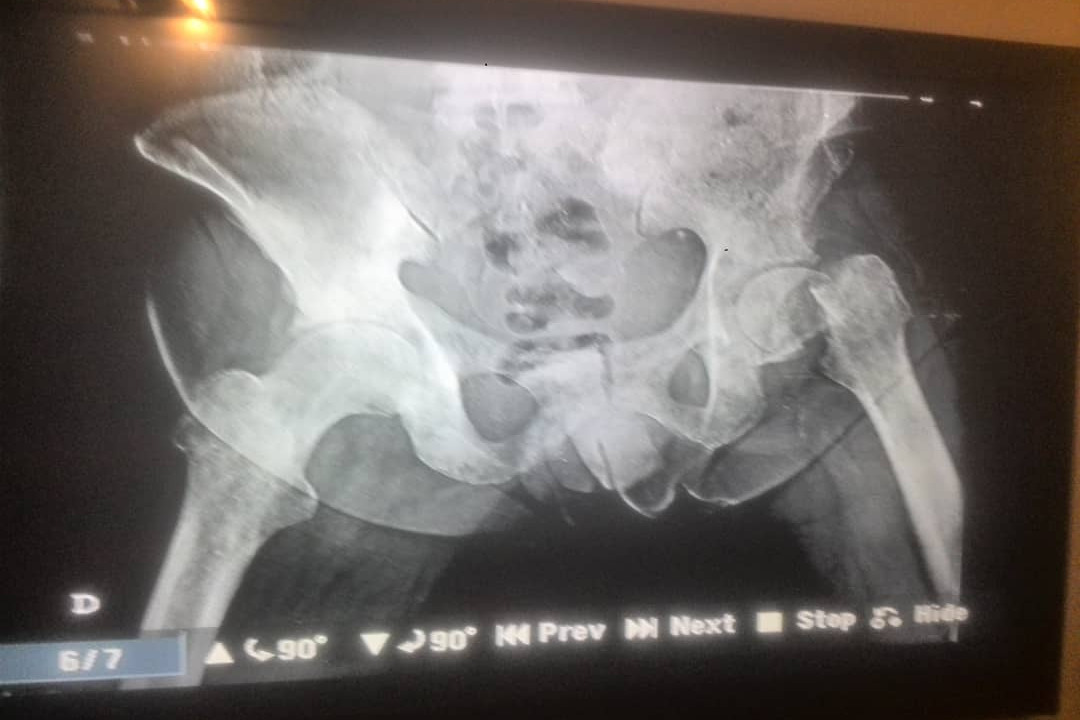

I’m Humberto Olivares, a 55 year old Venezuelan retired worker of the Los Andes University. A few months ago, I started having problems with my prostate. With the financial and logistical help of friends and family, i was taken to get tests done and treatment to solve my problem. Unfortunately, two months after going to a treatment center I suffered a bad fall. I was in bed without being able to walk, sleep or meet my most basic needs because of the pain. What I didn’t know is that I have a fracture in my hips, and a malignant tumor that has spread through many parts of my body.

To recover, I urgently need a thorax tomography, oncology treatment (radiotherapy and chemotherapy), an urgent surgery to implant the hip replacement, prostate biopsy, bone biopsy and more medical tests that due to my precarious economical situation and the terrible socioeconomic crisis that is a reality in Venezuela, I cannot cover those expenses. Due to hyperinflation I'm currently earning the equivalent of 2$ a month.  I’m in desperate need of help.

* 12 December 2020 Humberto got his thorax tomography exam done, picture of the result was added to the fundraiser photos